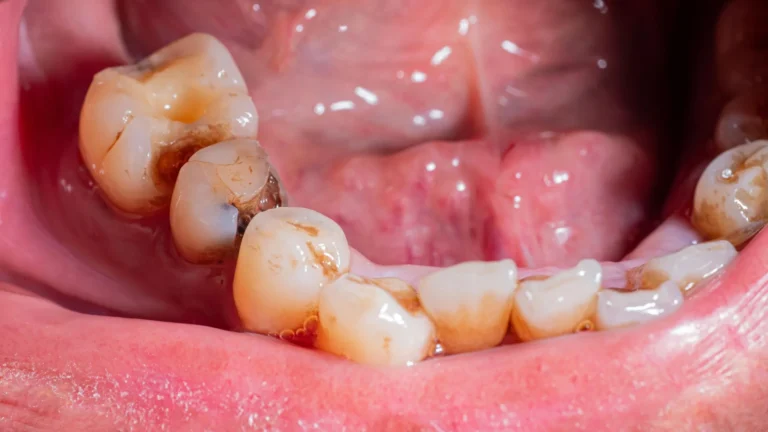

A groundbreaking advancement in dental care has emerged from Brazilian research laboratories, presenting a novel artificial saliva...